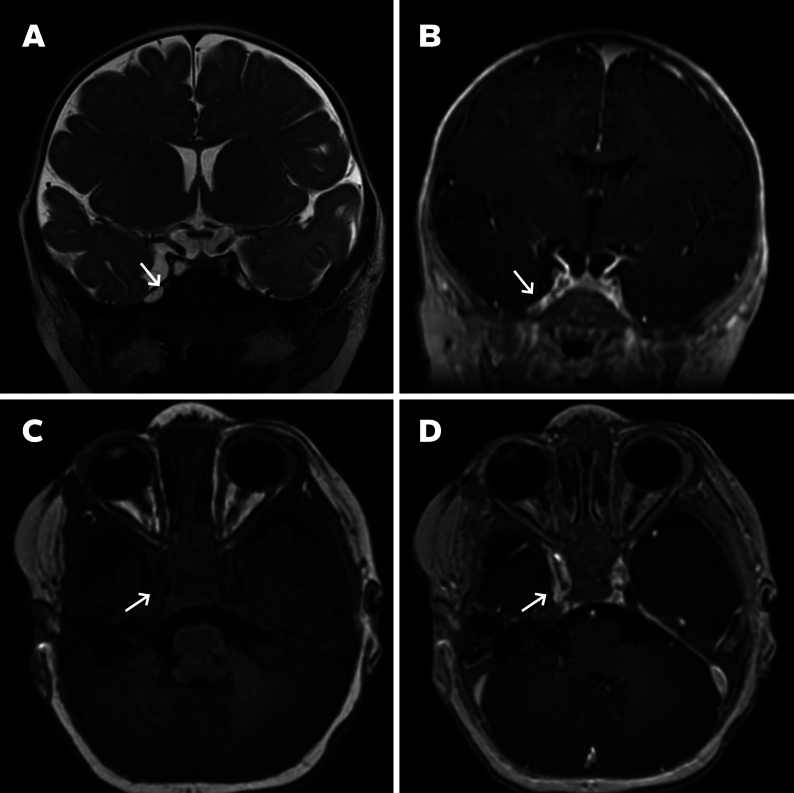

Observations: A 28-year-old female underwent routine fetal ultrasound at 32 weeks' gestation, revealing a 1.8-cm perithalamic lesion. Fetal MRI at 33 weeks confirmed an extra-axial mass in the right middle fossa with a dural attachment. Postnatal MRI on day 1 of life demonstrated imaging features consistent with an IH. Given the neonate's asymptomatic status, conservative management was pursued. Serial MRI at 10 weeks and 6 months showed progressive lesion regression, with near-complete resolution. The infant remained asymptomatic with normal neurodevelopmental progress.